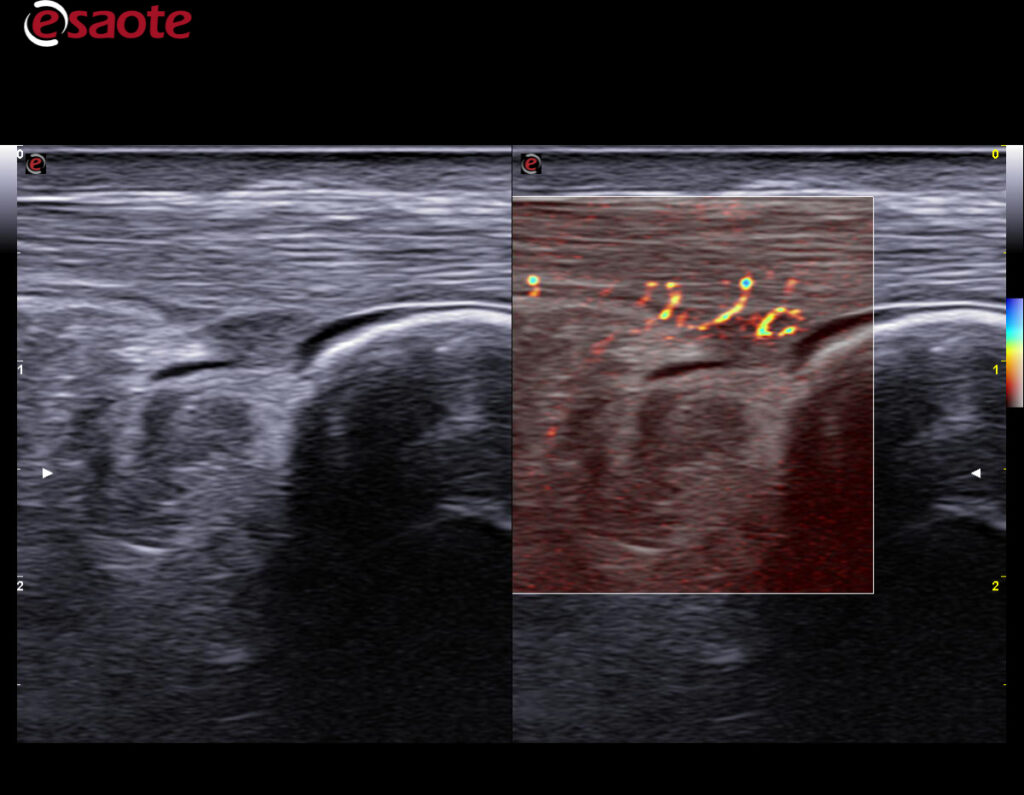

MSK/Rauma

MyLab X9o i spesialtilpasset versjon for MSK og revmatologi. Software er satt opp med spesialiserte presets for formålet. Ny 25 Mhz lineærprobe gir uovertruffen bilde-og dopplerkvalitet i overflaten.

Du ser strukturer tydeligere og mer detaljert enn tidligere. Ultrahøy «framerate» for dynamiske undersøkelser. En super sensitiv og stabil fargedoppler gir en dopplersensitivitet man ikke finner maken til, kombinert med markedets høyeste frekvenser på 25 Mhz. Den nye lineærproben med 4-25Mhz oppløsning, vil bli din nye favoritt. Gir fremragende og markedsledende bildekvalitet på helt overfladiske skanninger, samtidig med premium bildekvalitet ned til 2.5-3.0 cm. Dette er helt enestående for MyLab X90.

Ny bildeoptimaliseringsteknologi; X-View 5.0, fremhever hver eneste piksel, fjerner støy i bildet og forsterker overganger mellom strukturer. Dette gir en utrolig skarphet i bildet og hjelper deg å se hver eneste detalj. M-View 5.0 styrer signalene i flere retninger og legger informasjonen til bildet. Denne utrolige effekten reduserer artefakter og støy i tillegg til å forsterke bildeklarheten. Esaote er kjent for en ekstremt følsom farge – og powerdoppler og leveres nå i tillegg med MicroV. Alle modaliteter kan man styre signalet i ønsket retning, farge og følsomhet. Velg ønsket modul og du vil se mye der du tidligere ikke fikk frem dopplerinformasjon.